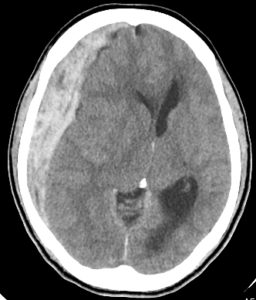

頭蓋骨内の硬膜と脳の間に血腫(血だまり)ができ、

脳を圧迫する症状

のこと。

硬膜とは、脳を包んでいる強度の高い膜のことで、頭蓋骨のすぐ内側にあり、くも膜の外側にある。

急性硬膜下血腫では、硬膜の内側で出血を起こして血だまり(血腫)ができ、血腫が脳を圧迫して様々な障害を引き起こす。

頭部CT:最も重要な検査であり、血腫の場所、大きさ、形状などを確認する。